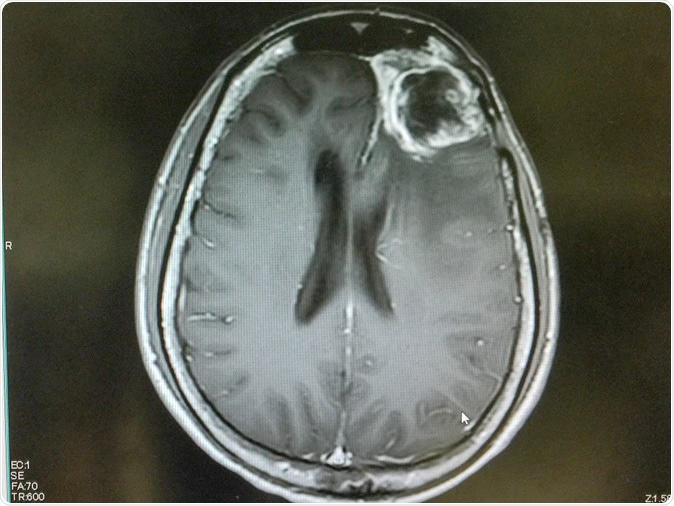

MRI brain show left frontal gliblastoma. Image Credit: O_Akira / Shutterstock